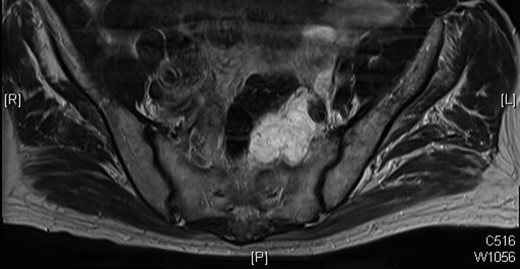

Given the extent of investigation to rule out another source of malignancy, the conclusion can be drawn that this is indeed a recurrence of the original villous adenoma that has undergone malignant change. This is a rare case that we believe is due to intra-operative seeding of tumour cells, as the original specimen was perforated. The time for malignant transformation from adenoma to carcinoma is indicative of the slow progression in some colorectal cancers [1, 2], presumably with mucin production (Figs 2 and 3). This case highlights the importance of obtaining a complete specimen with clear resection margins [3–5].

MRI scan of 2009 showing a mucinous mass in the left side of the pelvis below the anastomosis from his original sigmoid colectomy.